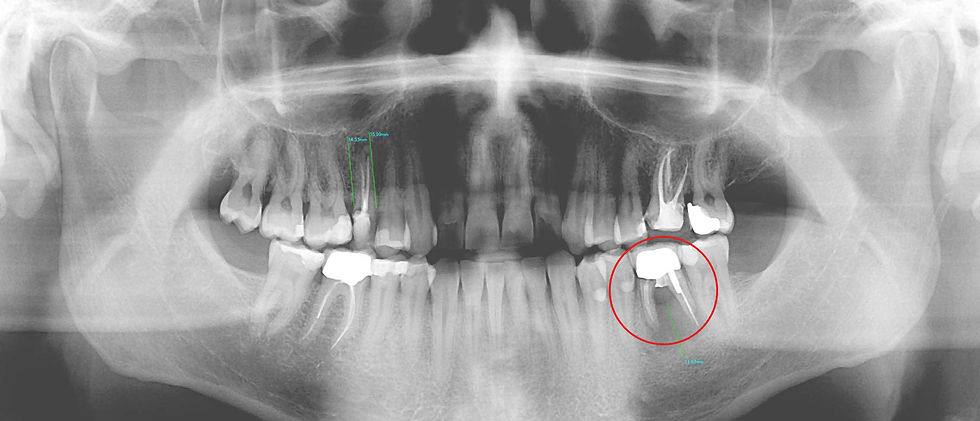

Initial orthopantomography: the element 3.6 shows a severe periodontal damage and an evident fracture of the mesial root. After an abscess, the patient underwent antibiotic therapy and the element was extracted.